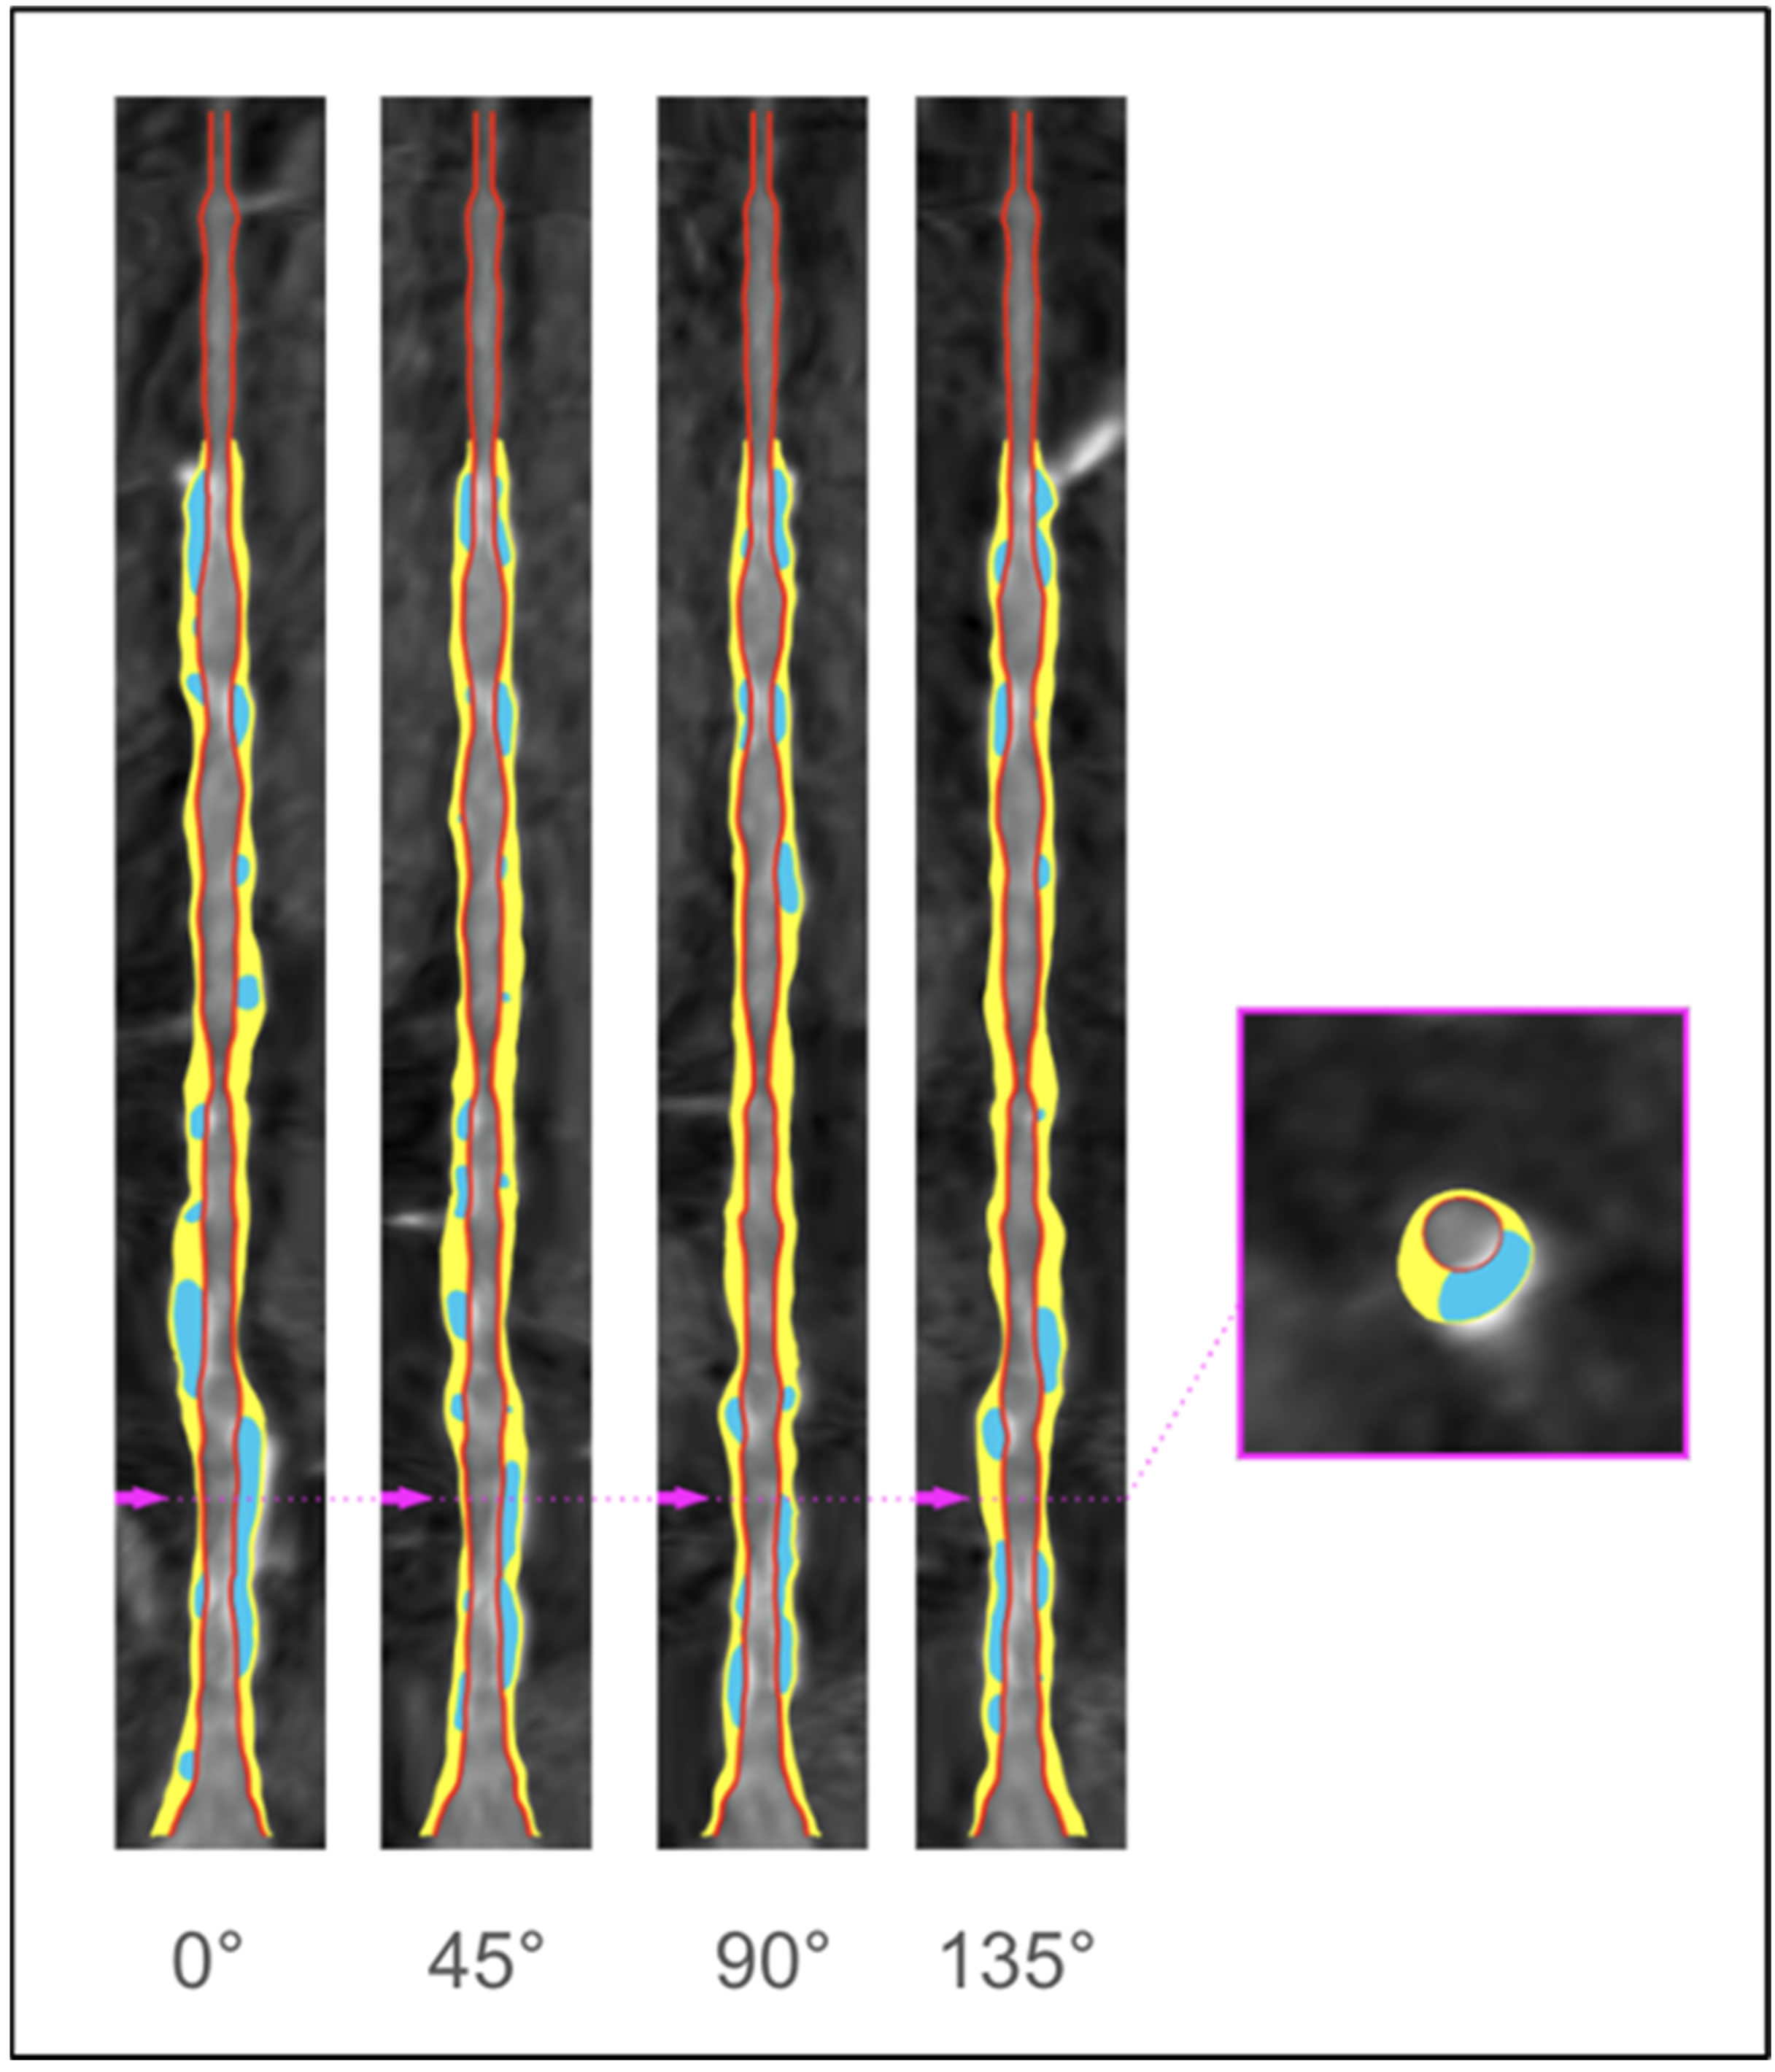

2. Anatomical Evaluation of Coronary Arteries